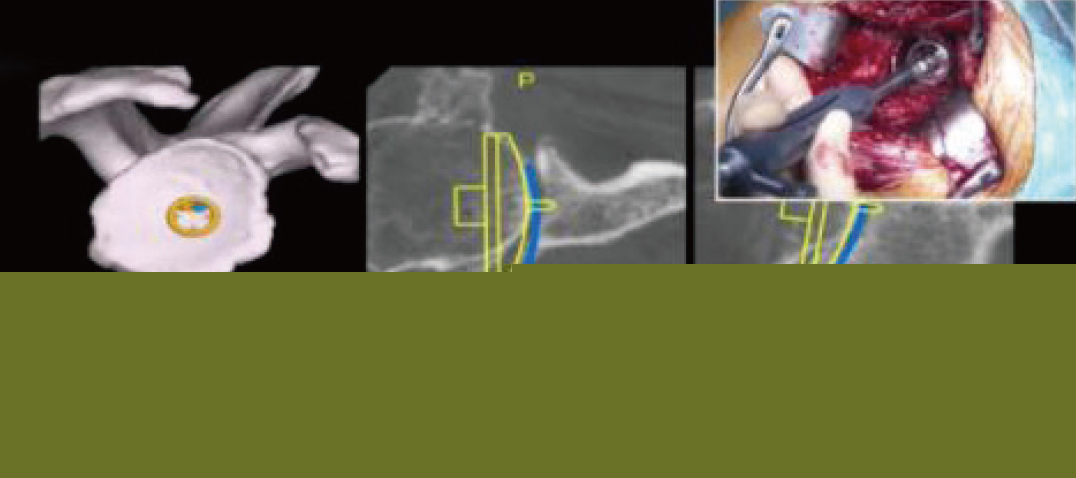

그림 2, 수술 시 환자의 CT를 수술 중 확인하며 이를 Navigation guided 하에 reaming 및 glenoid component를 삽입할 수 있다.

그림 3, Exactech Navigation guided RTSA - Preoperative planning software를 사용하여

수술 전 glenoid의 형태 를 파악하고 friedman line을 기준으로 Version, Inclination, Reaming depth를

결정하였으며 적절한 모양의 glenoid component 및 size를 선택하여 bony contact 면적률을 높였다.